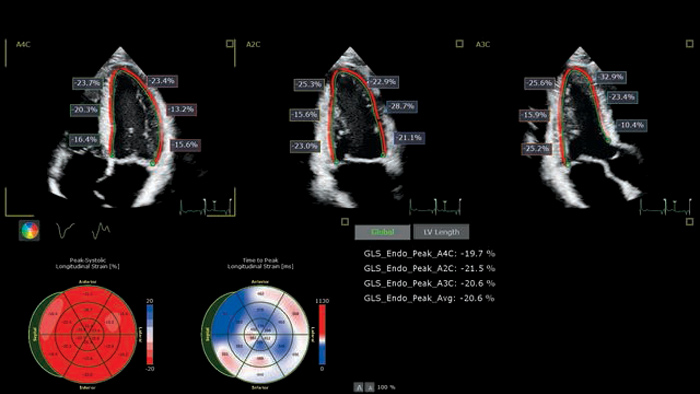

Streamline echocardiography workflow across your organization with Philips Ultrasound Workspace. Built on the legacy of the TOMTEC ARENA platform, it allows for greater efficiency in viewing, analysis and reporting by giving care teams the flexibility to adopt different workflows based on their current and future needs.

The EPIQ CVx is a dedicated cardiac ultrasound solution which brings significant advancements in functionality. This helps you deliver better care through higher processing power, exceptional imaging with more clarity & sharpness, improved exam efficiencies, complemented by the proven, robust quantification capabilities of Ultrasound Workspace.

Cardiac imaging modalities support a more confident stratification of cardiovascular toxicity while serving as a powerful baseline reference for treatment and long-term follow-up.